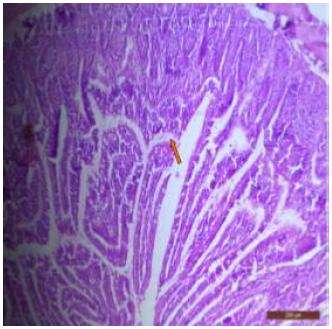

Light Microscopic Examination

The duodenum of control rat showed histological features such as presence of different layers such as mucosa, submucosa, muscularis and serosa. The lining of epithelium of microvilli was composed of many cell types such as goblet cells, Paneth cells and absorptive columnar epithelial cells (Figure 1). Brünner’s glands were seen in the submucosal region of the duodenum which secrete alkaline fluid containing mucin (Figure 2). The rats treated with 600mg/kg b.w./day for 40 days revealed thickened and scattered villi (Figure 3). Hypertrophy of goblet cells and damaged crypts were also observed. (Figure 4). The necrotic Brünner’s gland showed inflammation and dilation of spaces (Figure 5).

Figure 1: T.S. of duodenum of control rat showing crypts (↑), closely packed microvilli (↑), well developed submucosa and muscularis externa. H&E × 100.

There was disruption in the villus architecture with crypt loss. The submucosa, muscularis externa and outer serosa were undifferentiated and were not clearly seen (Figure 6). There was marked villous atrophy, characterized by the shrinking and flattening of the intestinal villi. Additionally, mucosal erosion was also evident, indicating the wearing away of the protective mucosal layer (Figure 7). The duodenal tissues showed widespread disruption, with visible signs of structural disorganization and inflammation (Figure 8). The jejunum of control rat showed distinctive layers, i.e; mucosa, submucosa, muscularis and serosa (Figure 9). The jejunal mucosa was formed of epithelium, lamina propria and muscaris mucosa. The mucosa appeared as finger like projections with a core of connective tissue covered with enterocytes. Goblet cells were also seen in between the cells which are specialized type of epithelial cells, secrete mucus to neutralize the acids produced by stomach (Figures 10,11).

In fluoridated rats damaged and broken villi, focal intervillous haemorrhages and ulceration was present (Figure 12). There was shortening and flattening of some of the villi (Figure 13), distorted crypts, large swollen goblet cells lined by columnar epithelium with wide spaces were present (Figure 14). Distortion of different layers of mucosa with the loss of villous architecture and shedding of surface epithelium was seen in the jejunum of fluoridated rats (Figure 15). The villus architecture was notably disturbed, with a marked loss of crypts. Furthermore, there was a noticeable decrease in the number of goblet cells (Figure 16). The villi appeared scattered and fragmented, indicating a disruption in their typical architecture. Reduction in size of intestinal glands highlighted the detrimental impact of fluoride exposure on the intestinal morphology of rats (Figure 17).

Figure 12: T.S. of jejunum of rat treated with 600 mg NaF/kg b.w./day for 40 days showing ulceration, focal intravillous hemorrhages and broken villi (↑). H&E × 100.

The ileal mucosa of control rat was built up of numerous folds forming the villi, through which connective tissue of the lamina propria containing tubular glands i.e., crypts of Leiberkühn were present (Figure 18). The epithelial lining of the villi was composed of Paneth cells and intestinal glands (Figure 19). In fluorotic rats, there were abnormal shaped, damaged and broken villi with bulbous tips. Lymphatic dilation and haemorrhaged in lamina propria were also seen (Figure 20). In the ileal mucosa, prominent inflammation, distortion of crypts with shredded cells inside the crypts were visible (Figure 21). Swollen and necrotic crypts were present (Figure 22). The ileal tissue showed disruptions in the normal mucosal architecture with signs of villous atrophy and cell infiltration (Figure 23). Lymphatic infiltration was prominent and numerous enlarged lymph nodules appeared in lamina propria of villi. There were ill-defined cell boundaries, vacuolated cytoplasm and pyknotic nuclei (Figure 24).